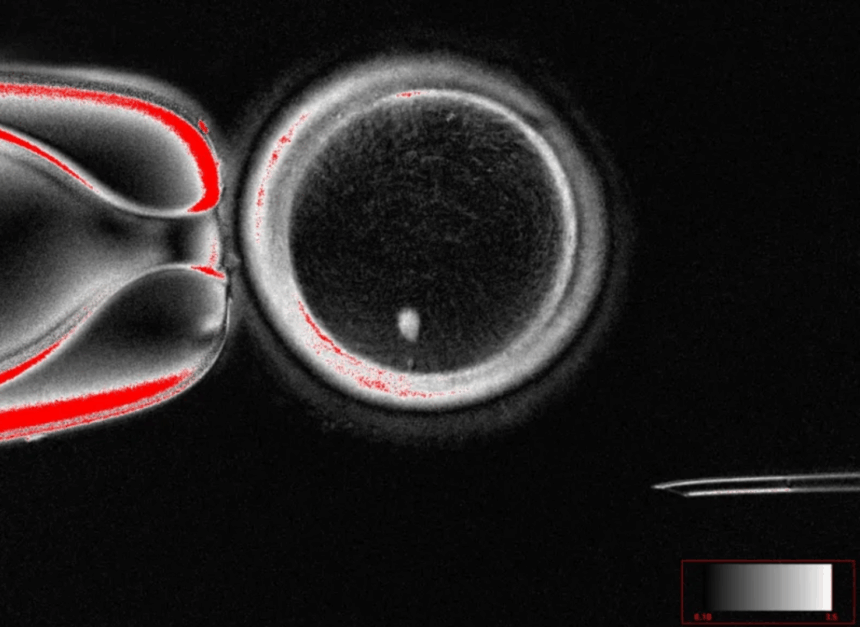

Në këtë studim, shkencëtarët përdorën një proces të ri të quajtur “mitomeiosis”, i cili lejon qelizën të heqë një set kromozomesh, duke e bërë atë haploide, si një qelizë vezë natyrale. Nga ky eksperiment, u krijuan 82 qeliza vezë funksionale, të cilat më pas u fertilizuan në laborator. Rreth 9% e tyre arritën fazën e blastocistëve, një stad i hershëm i zhvillimit embrional.